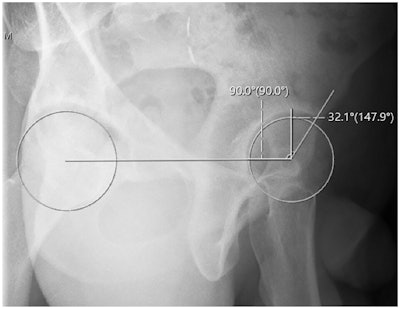

In this study, the team investigated whether their novel method, which uses standard x-ray viewing tools to generate a true horizontal reference line and best-fit circles on each femoral head, may allow for more precise assessments.

Anterior center edge angle measurement utilizing a horizontal reference line. Orthopedic Journal of Sports MedicineThree investigators retrospectively reviewed the x-rays of 21 patients with a diagnosis of hip pain. The mean age of the patients was 34, and 71% were female. On two separate occasions, the reviewers recorded both traditional ACEA measurements and novel ACEA measurements.

According to the results, the mean ACEA value obtained using the traditional method was 39.72°, and the mean ACEA value obtained using the novel method was 37.68° (p = 0.36). Intrarater reliability for the novel method was found to be strong (ICC = 0.805-0.966) in all instances.

Meanwhile, interrater reliability was also found to be strong in all instances using the horizontal reference line (ICC = 0.831-0.902), but was weak for two of three reviewers using the traditional method (ICC = 0.42, 0.585, and 0.769), the researchers reported.

“This study demonstrated that utilization of a horizontal reference line in the false-profile view when measuring the ACEA yielded more reproducible calculations, both between separate physicians and within a physician's individual measurements, compared with the traditional measurement method,” the group wrote.